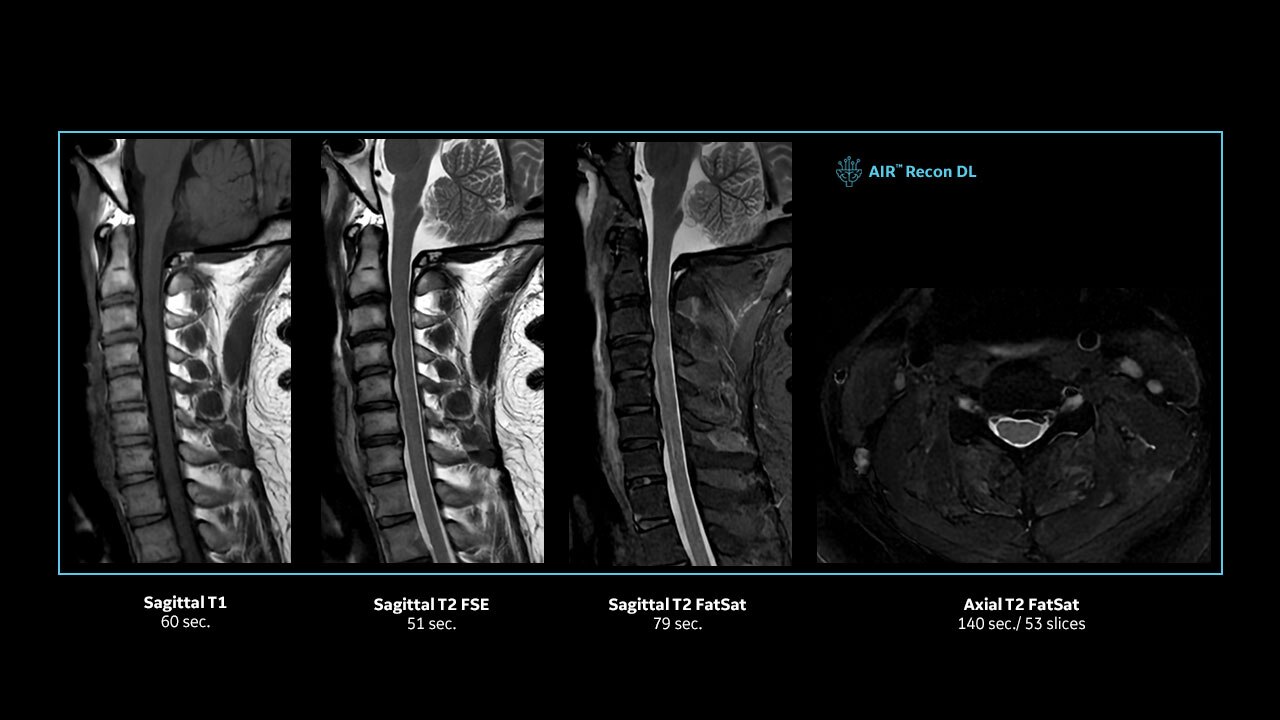

Achieve pin-sharp image quality with pioneering AIR™ Recon DL AI technology

With access to the latest advanced AI technology, you can scan all anatomies and achieve pin-sharp images. Our pioneering Deep Learning-based reconstruction algorithm AIR™ Recon DL accelerates scan time and puts patients at ease.